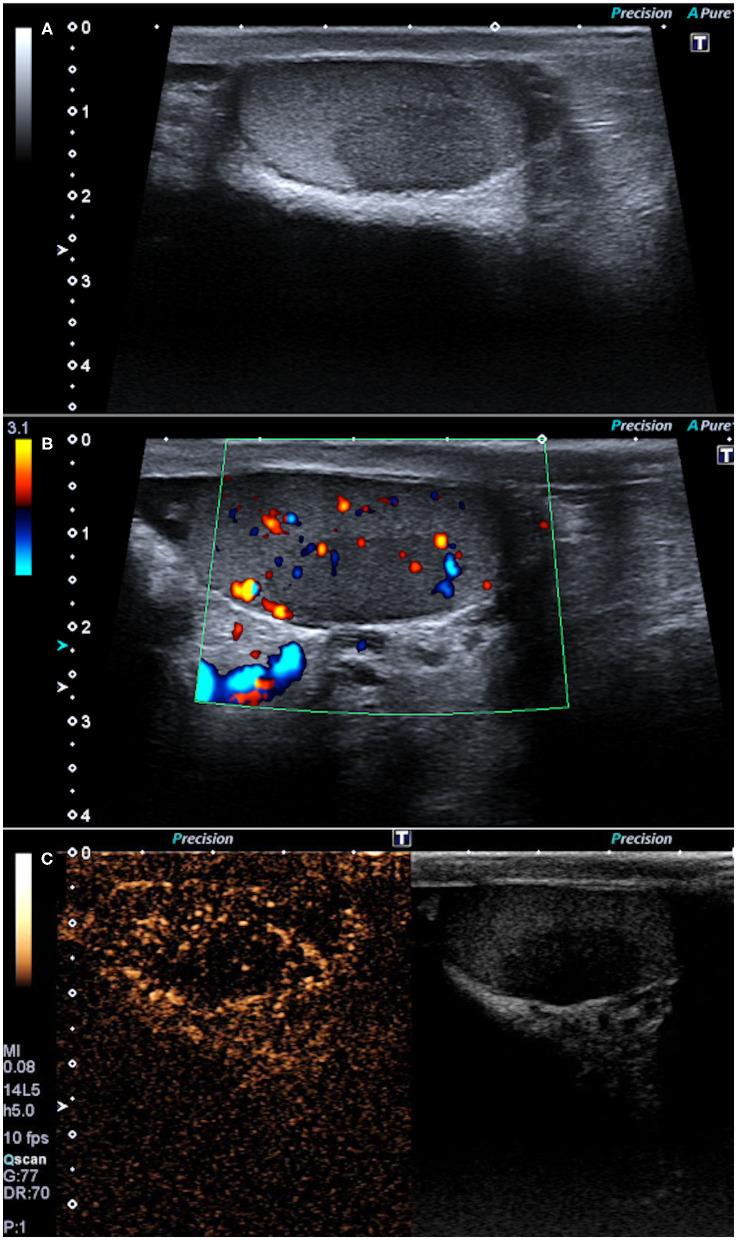

Sarcoidosis is a multisystemic disease histologically characterized by non-caseating epithelioid granulomas and multinucleated giant cells; the etiology is still uncertain, and likely related to a complex interplay between environmental and genetic factors. The genitourinary system is affected in fewer than 0.2% of all clinically diagnosed cases of sarcoidosis and in 5% of those identified in autopsy studies. In this report, we describe a case of a 42-year-old male with one hypoechoic lesion per testis on B-mode evaluation; contrast-enhanced ultrasound (CEUS) on both lesions was carried out. During the early phase, the masses showed a hypovascular appearance as compared to the surrounding testicular tissue, maintaining the hypo-enhancement in the late phase. Tissue biopsy for pathological evaluation confirmed testicular sarcoid involvement, showing non-caseating granulomas. Allowing visualization of testicular microvascularisation, CEUS may play an important role in excluding malignancy, avoiding unnecessary aggressive treatment for benign conditions, such as sarcoidosis. A review of the literature of reported cases since 2004 of sarcoidosis involving the testis is also included.

结节病是一种多系统疾病,组织学特征为非干酪样上皮样肉芽肿和多核巨细胞;其病因仍不确定,可能与环境因素和遗传因素之间的复杂相互作用有关。在所有临床诊断的结节病病例中,泌尿生殖系统受累的比例不到0.2%,而在尸检研究中发现的病例中这一比例为5%。在本报告中,我们描述了一例42岁男性,B超评估显示每个睾丸有一个低回声病变;对两个病变均进行了对比增强超声(CEUS)检查。在早期阶段,与周围睾丸组织相比,肿块表现为低血供,在晚期阶段仍保持低增强。组织活检进行病理评估证实睾丸结节病累及,显示非干酪样肉芽肿。CEUS能够显示睾丸微血管情况,在排除恶性肿瘤、避免对结节病等良性疾病进行不必要的积极治疗方面可能发挥重要作用。本文还对2004年以来报道的累及睾丸的结节病病例文献进行了综述。